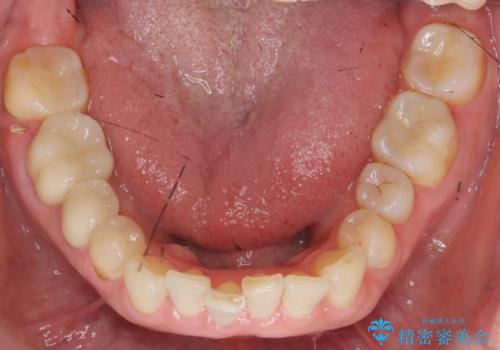

治療後、明るくなった口腔内を見て大変満足いただくことができました。

色調だけでなく、精密な治療を行うことで虫歯の再発の確率を下げることも可能になります。